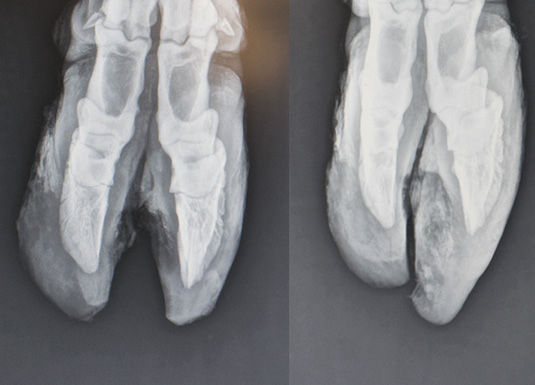

Tanken om korleis klauvvekst påverkar beina i klauven, svirra rundt i hovudet på den engasjerte fagmannen. Han avklarte med bonden, sette att nokre av dei kyrne som hadde mest vekst, og kontakta veterinær Tore Malmei, som han visste hadde røntgenapparat. Han inviterte sine klauvskjerar-kollegaer i regionen, nokre rådgjevarar og eit par dyrlegar til eit lite mini-seminar.

Dei erfarne klauvskjerarane var overraska over kor store utslag sjølv «vanleg» vekst, hadde på posisjonen til klauvbeinet. Ingen av kyrne som vart skorne, viste halthet eller signal på smerte i forkant.

Konklusjon: klauvene må skjerast lenge før ein har tenkt. Minst to gonger i året.